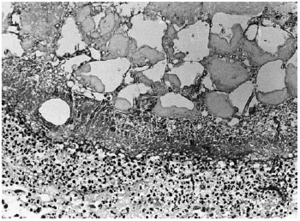

A los pocos días le apareció una lesión nodular dolorososa en el costado, de 6 cm de diámetro, de superficie eritematosa y crecimiento rápido. Se realizó biopsia cutánea, enviando muestra para cultivo y para estudio histopatológico. En el cultivo se identificó Aspergillus flavus y el examen histológico mostraba en piel una lesión centrada en el tejido celular subcutáneo (fig. 1) donde se observaba un área de necrosis amplia de los lobulillos adiposos (figs. 2 y 3), en cuyo interior se reconocían abundantes nidos de hifas fúngicas tabicadas, positivas con las tinciones de PAS y metenamina plata.

Fig. 1.--Imagen panorámica donde se observa en el tejido celular subcutáneo un área de rarefacción con necrosis grasa extensa.